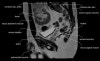

- Sagittal section

Sagittal PD fat suppression is sensitive to fluid that may be present with AVN or stress fractures.